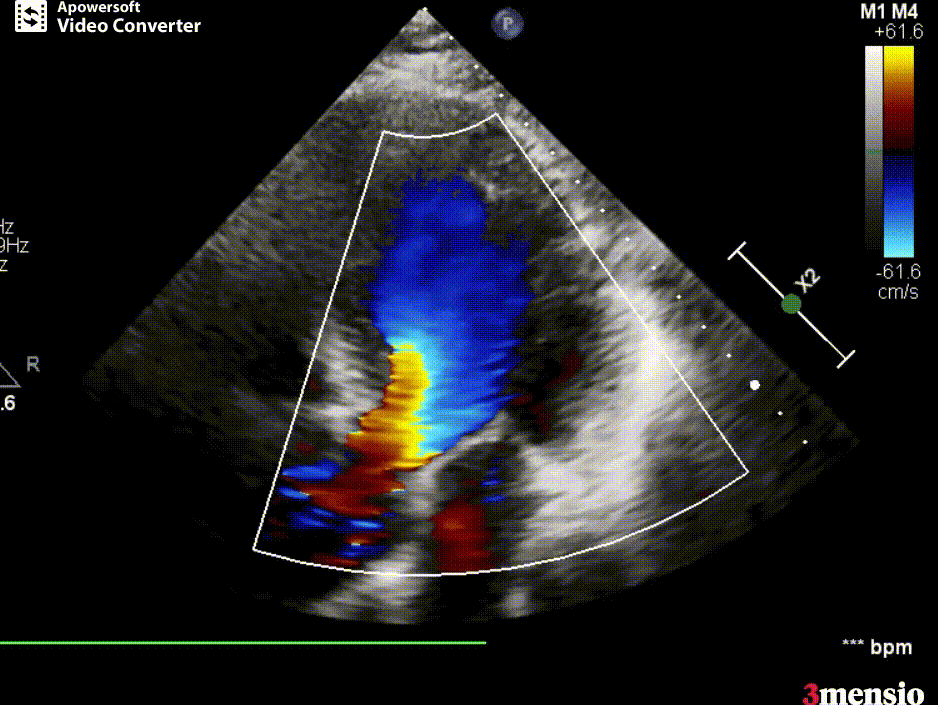

患者为71岁男性,因“活动后胸闷乏力6个月,加重1月余”入院。查体:血压146/54mmHg,心率81次/分,心律齐,于R2可闻及中度哈气样舒张期杂音。超声心动图示:主动脉重度返流;左室壁节段性运动不良;左心扩大、室间隔增厚,左室充盈异常。术前CT评估显示,LVOT周径24.9mm,面积443.3m²;瓣膜无钙化,主动脉瓣瓣环面积522.1m²。综合考虑LVOT较瓣环偏小,遂选用JS/TAVI 27 Ken-Valve人工瓣膜进行经心尖TAVI手术。

术前超声影像图

术后超声影像图